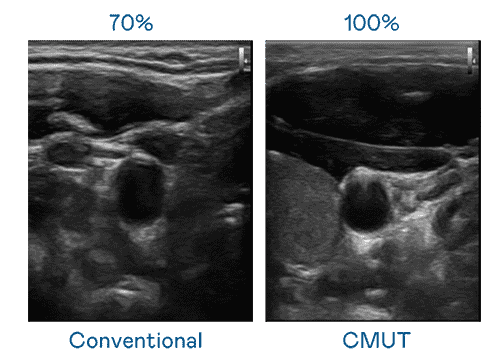

CMUT 技术是一种用电容式微机电元件来产生超音波讯号的技术。。。与传统 PZT 压电式技术相比,,,CMUT 频宽增加 30%,,更宽频的超音波讯号让影像解析度大幅提升,,,是实现高影像品质医疗超音波扫描、、、促进精准医疗发展的关键技术。。

大频宽带来超清晰影像

超音波影像的解析度高低,,,,首先取决于探头能发出的讯号频宽。。z6mg·人生就是博 CMUT 可提供高清晰的超音波讯号,,提供高频宽、、高灵敏度、、影像纹理细节更高的超音波影像,,协助医护人员缩短影像判读时间及利用精准的医疗影像进行诊断。。